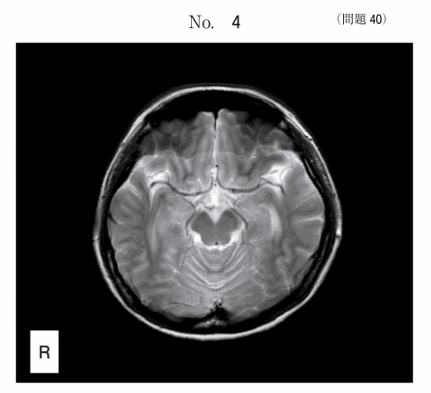

午前/問題40

高速スピンエコー法による頭部MRI T2強調像別冊No. 4を別に示す。中大脳動脈内が低信号に描出される理由はどれか。

1.位相分散

2.ブラーリング

3.インフロー効果

4.ミスレジストレーション

5.トランケーションアーチファクト